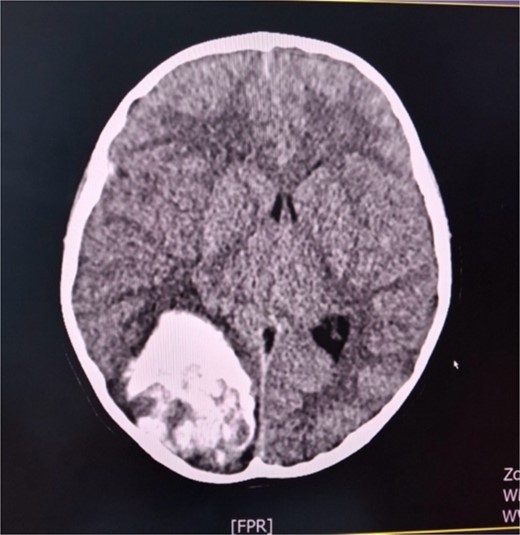

A 6-year-old female child in a comatose state with two dilated pupils as an emergency case was brought to the University Clinic of Neurosurgery. A cerebral CT scan showed a hemоrrhagic voluminous tumor in the right occipital region (Fig. 1). Immediately, she underwent a craniotomy for maximum tumor reduction. During postoperative days, she was stable, a control cerebral MRI scan with contrast was done, and a second surgery for tumor reduction was decided to be done. The findings of the histopathologic examination of the tumor were consistent with an embryonal tumor of CNS NEC/NOS (not elsewhere classified/non-otherwise specified) (CNS WHO grade 4). A spinal tap was performed, and the microbiological findings of the cerebrospinal fluid cultures were negative. Cerebrospinal fluid cytology was within normal limits. She was referred to a pediatric oncologist. After the first cycle of chemotherapy, she developed signs of hydrocephalus and meningism. The patient underwent external ventricular drainage with the insertion of a middle-pressure valve.

Axial cerebral CT scan shows massive hemorrhaging tumor in the right occipital region with perifocal oedema.